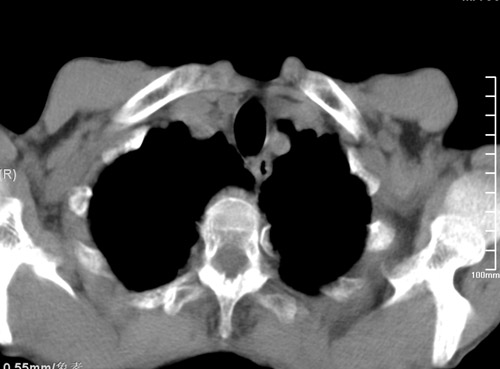

标题: CT17529:男 76 胸背部不适半月 胸透支气管炎 行CT检查 [打印本页]

标题: CT17529:男 76 胸背部不适半月 胸透支气管炎 行CT检查

意见 老年肺 少许炎症 肺大泡 右肺门略大 但支气管通畅  请各位高手指教如何下意见